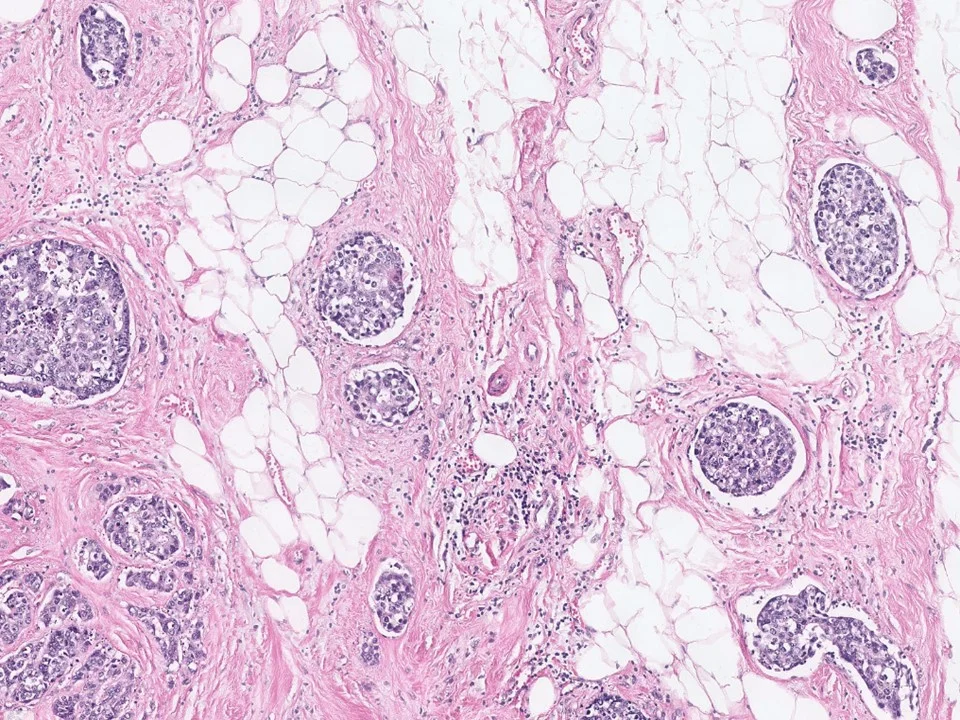

Invasive Micropapillary Carcinoma

Histologically, invasive micropapillary carcinoma is characterized by clusters of cells with a micropapillary or tubular-alveolar arrangement. The clusters of cells appear to be suspended in clear spaces.

Unlike true papillary lesions, no fibrovascular cores are identified. The clusters of cells have an "inside-out" arrangement, with the apical surface polarized to the outside, toward the stroma. This feature can be highlighted by EMA immunostain.

The majority of invasive micropapillary carcinomas are ER+, and about half are PR+. HER2 overexpression has been reported in up to one-third.

Metastatic carcinomas with micropapillary pattern, such as those from the ovaries, lungs, or bladder, should be considered in appropriate clinical settings. While the majority of invasive micropapillary carcinomas demonstrate a DCIS component (~70%), metastatic carcinomas will not show DCIS (as expected).